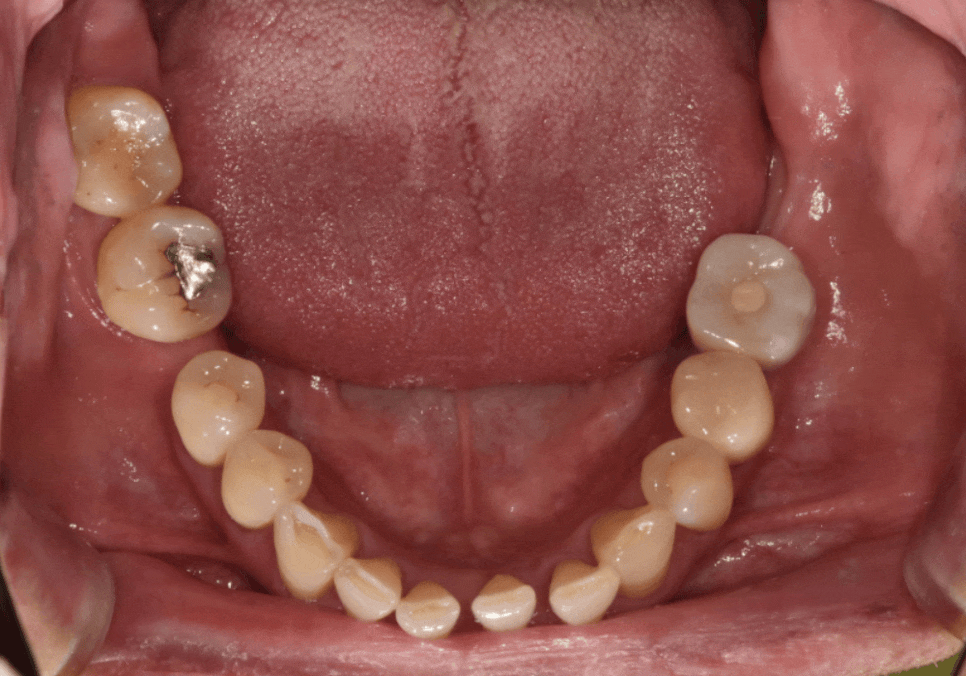

결국, 고민 끝에 교합을 크게 바꾸지 않으면서

빈 곳을 채우는 브릿지로 치료를 결정했습니다.

현재 치아가 많이 기울어져 있기 때문에

치아를 깎는 양이 많을 것으로 예상되었는데요~

시린 증상을 방지하기 위해

꼼꼼하게 신경치료를 선행한 뒤

브릿지로 마무리해드렸습니다~

230704